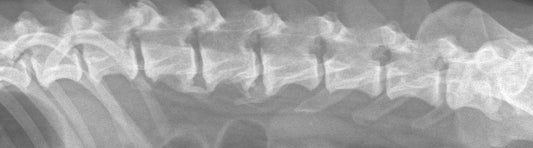

Spondylose bei Hunden

Wenn sich das Bewegungsmuster deines Hundes plötzlich verändert, er Treppen meidet oder nicht mehr springen kann, könnte eine Spondylose-Erkrankung vorliegen. Hier erfährst du, wie du Spondylose bei deinem Hund erkennen...